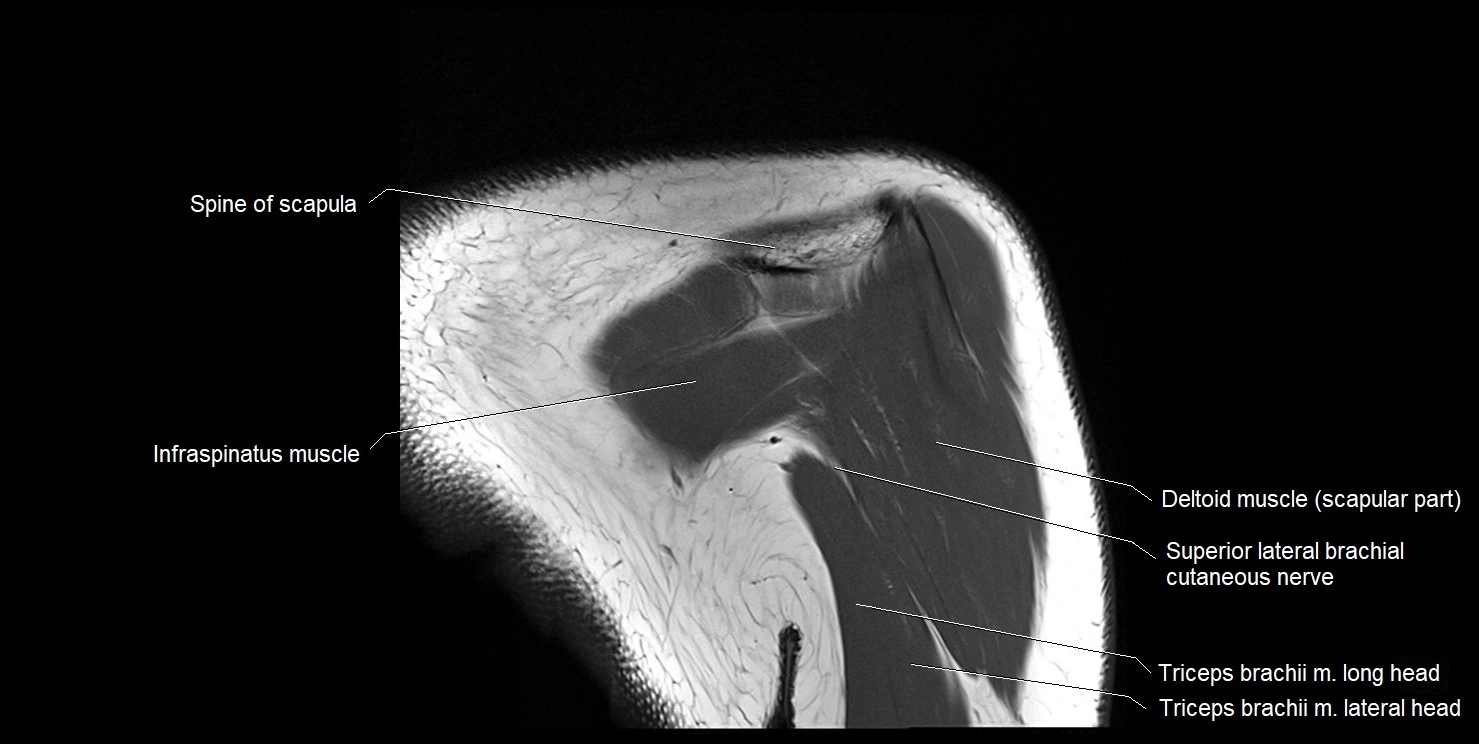

CT image

image